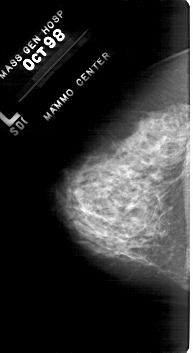

A_1819_1.RIGHT_MLO

LEFT_MLO LINES 5491 PIXELS_PER_LINE 2956 BITS_PER_PIXEL 12 RESOLUTION 43.5 NON_OVERLAY